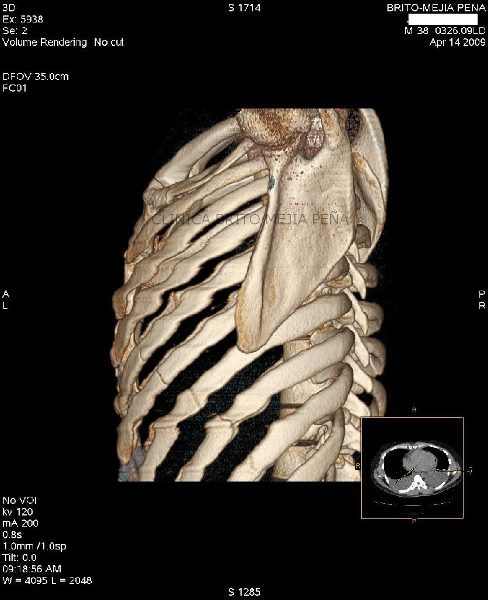

Instrumentalización columna 3D

Instrumentalización columna ósea